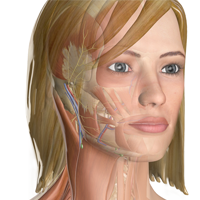

Know Your Anatomy